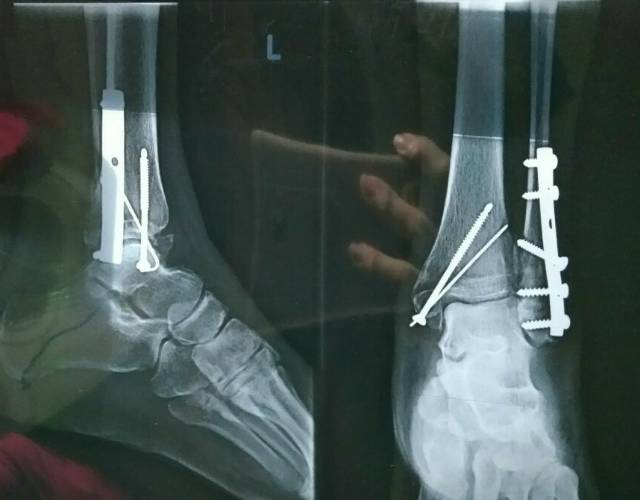

Pen akan digunakan untuk penyembuhan patah tulang jika pemulihan dengan gips tidak mencukupi atau tulang tidak bisa pulih dengan benar.

Prosedur Pemasangan Pen Untuk Mengobati Patah Tulang Alodokter

Pemasangan Pen Tulang Prosedur Manfaat Risiko Dan Efek Samping Good Doctor Tips Kesehatan Chat Dokter Beli Obat Online

Mungkinkah Pen Tulang Patah Dan Rusak Bagaimana Jika Itu Terjadi